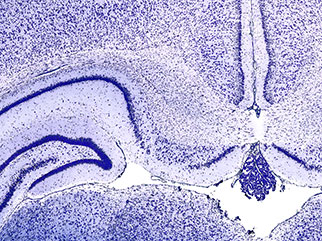

Unterrichtsmodul „Cortex — Zellen und Schichten“

Die Schüler:innen erarbeiten anhand der Nissl-Färbung die Organisation des Cortex. Dafür betrachten sie unterschiedliche Zelltypen und quantifizieren deren Packungsdichte in verschiedenen Bereichen. Weiterhin setzen sich die Schüler:innen mit der charakteristischen Schichtung im Nervengewebe auseinander.